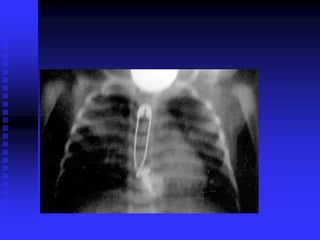

Foreign Body Airway Obstruction

FBAO

FBAO: High Risk Groups

 > 90% of deaths: children < 5 years old

 65% of deaths: infants

FBAO: Signs/Symptoms

 Suspect in any previously well, afebrile

child with sudden onset of:

Respiratory distress

Choking

Coughing

Stridor

Wheezing

FBAO: Management

 Minimize intervention if child conscious,

maintaining own airway

 100% oxygen as tolerated

 No blind sweeps of oral cavity

 Wheezing

Object in small airway

Avoid trying to dislodge in field